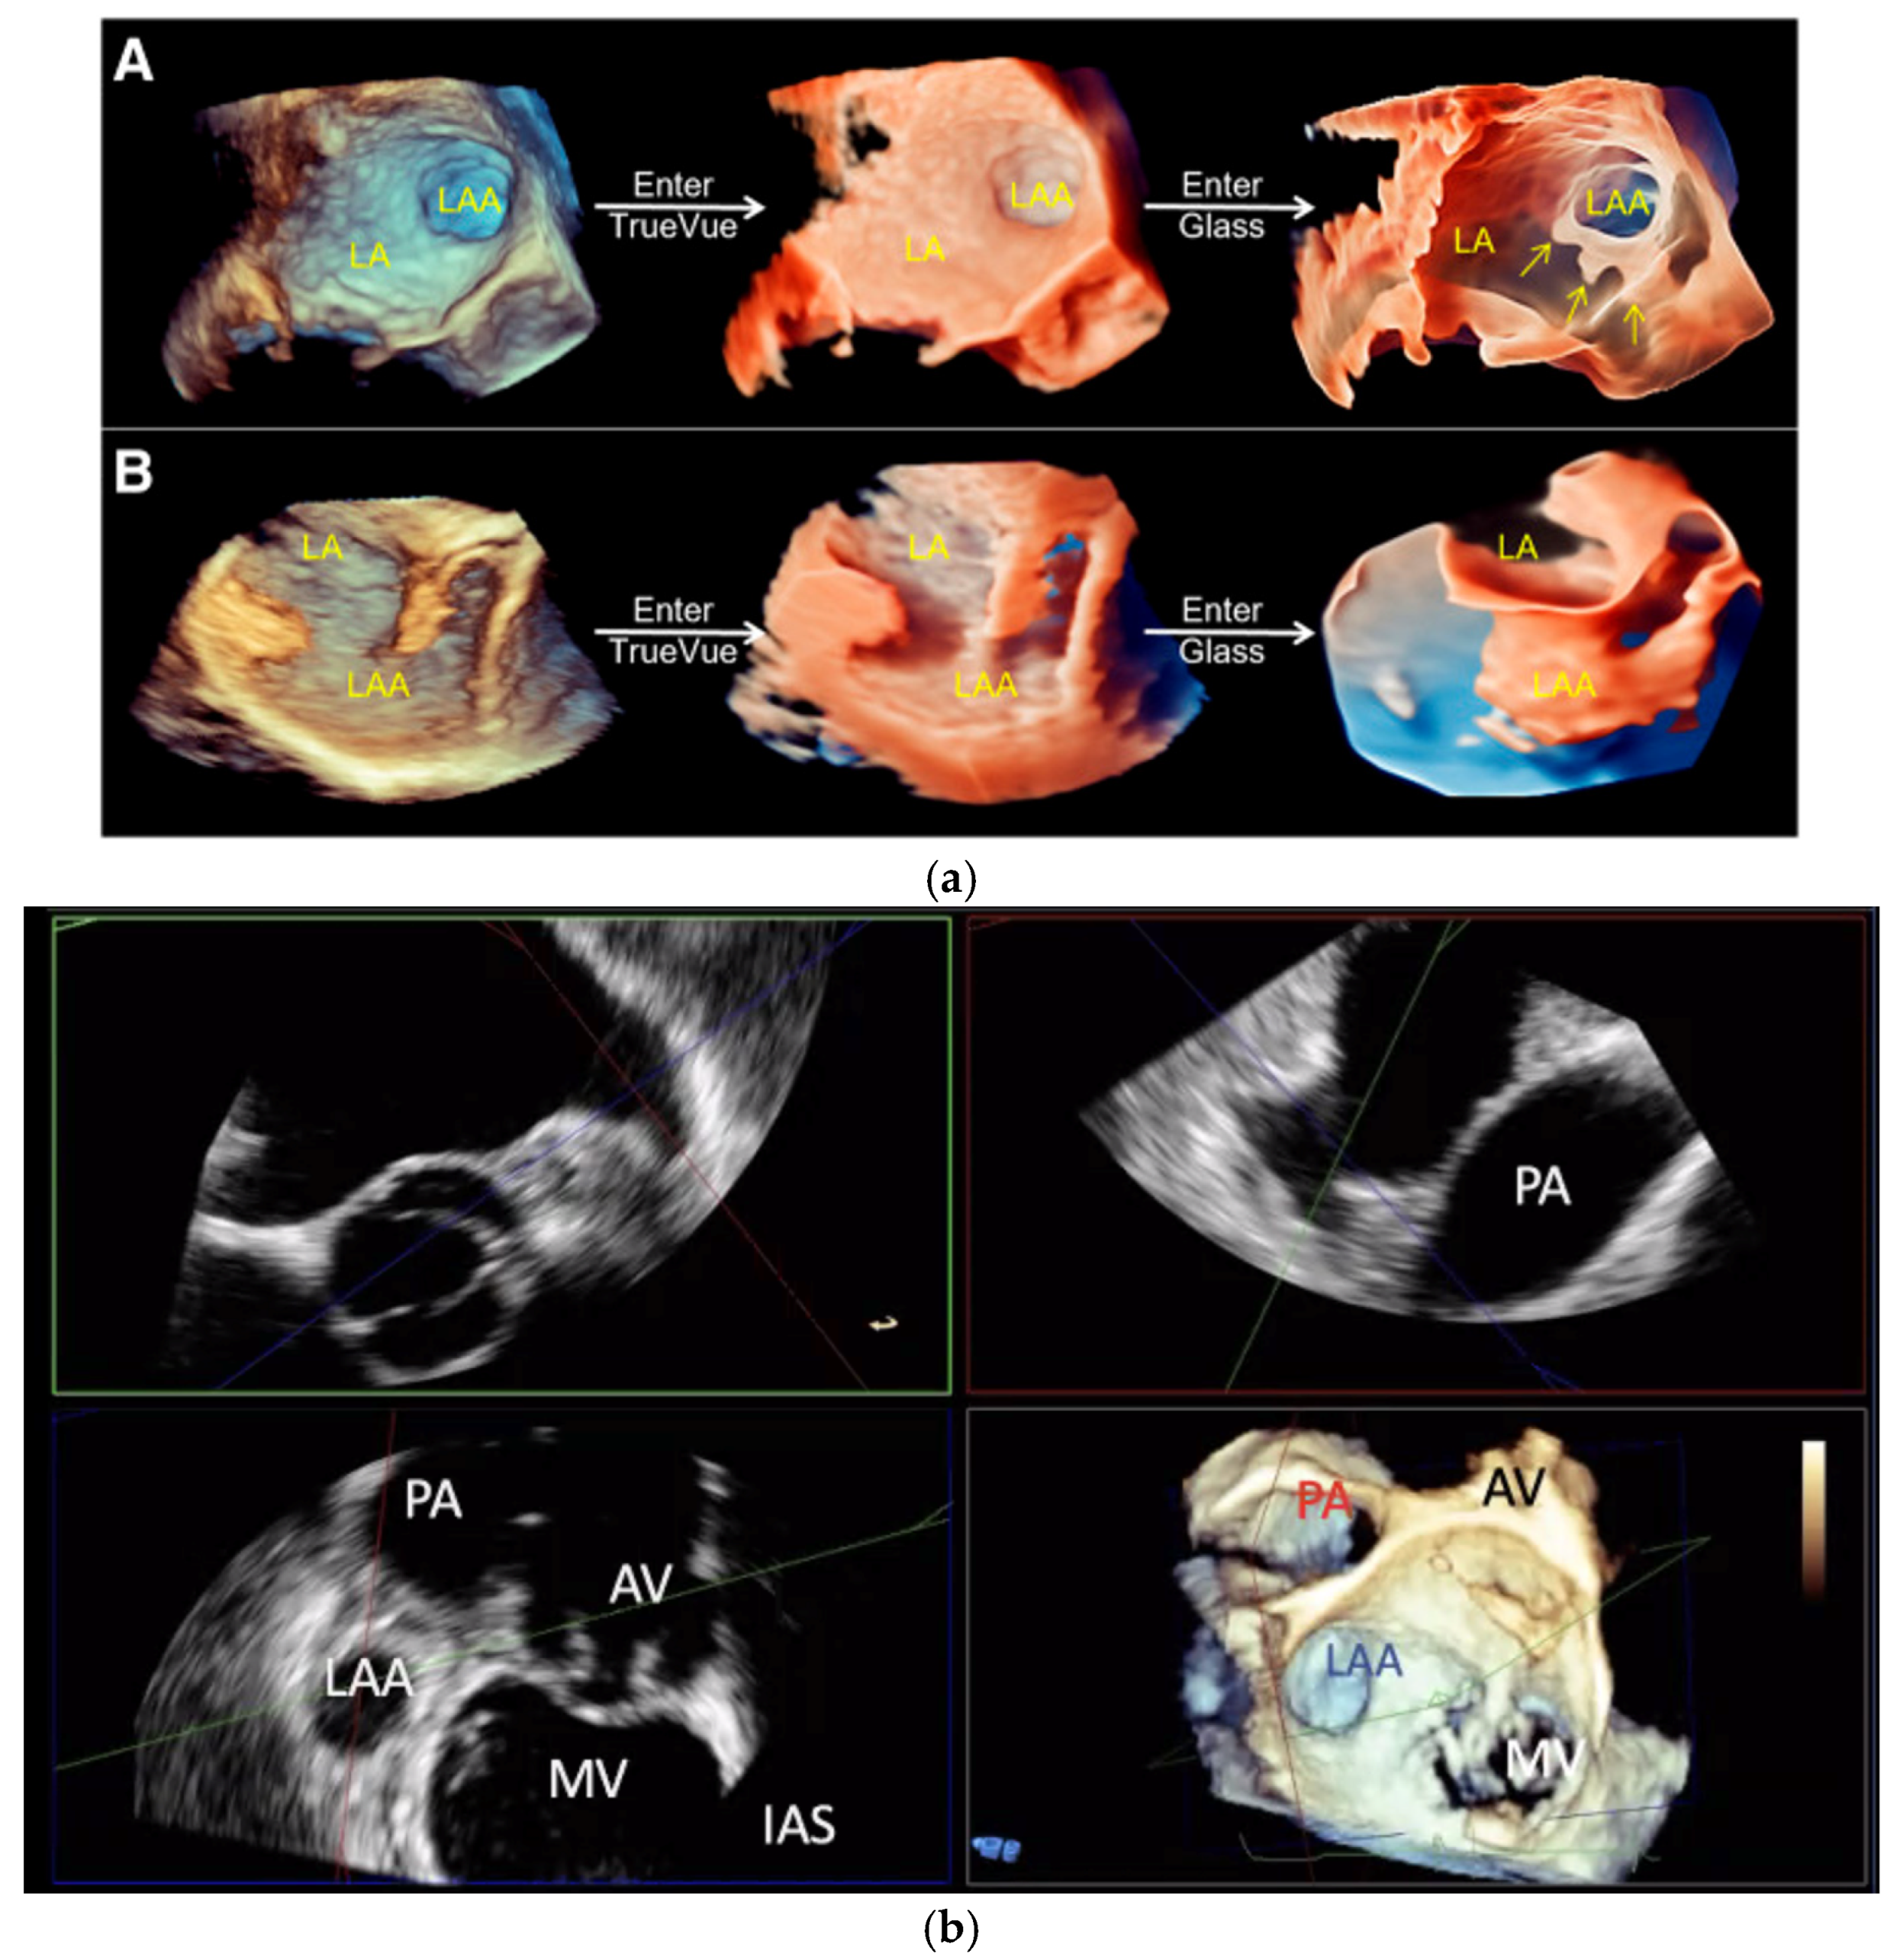

2.2.1. LAA Thrombus Assessment

2.2.2. LAA Measurements (Anatomy and Morphology)

2.2.3. Intra-Procedural TOE